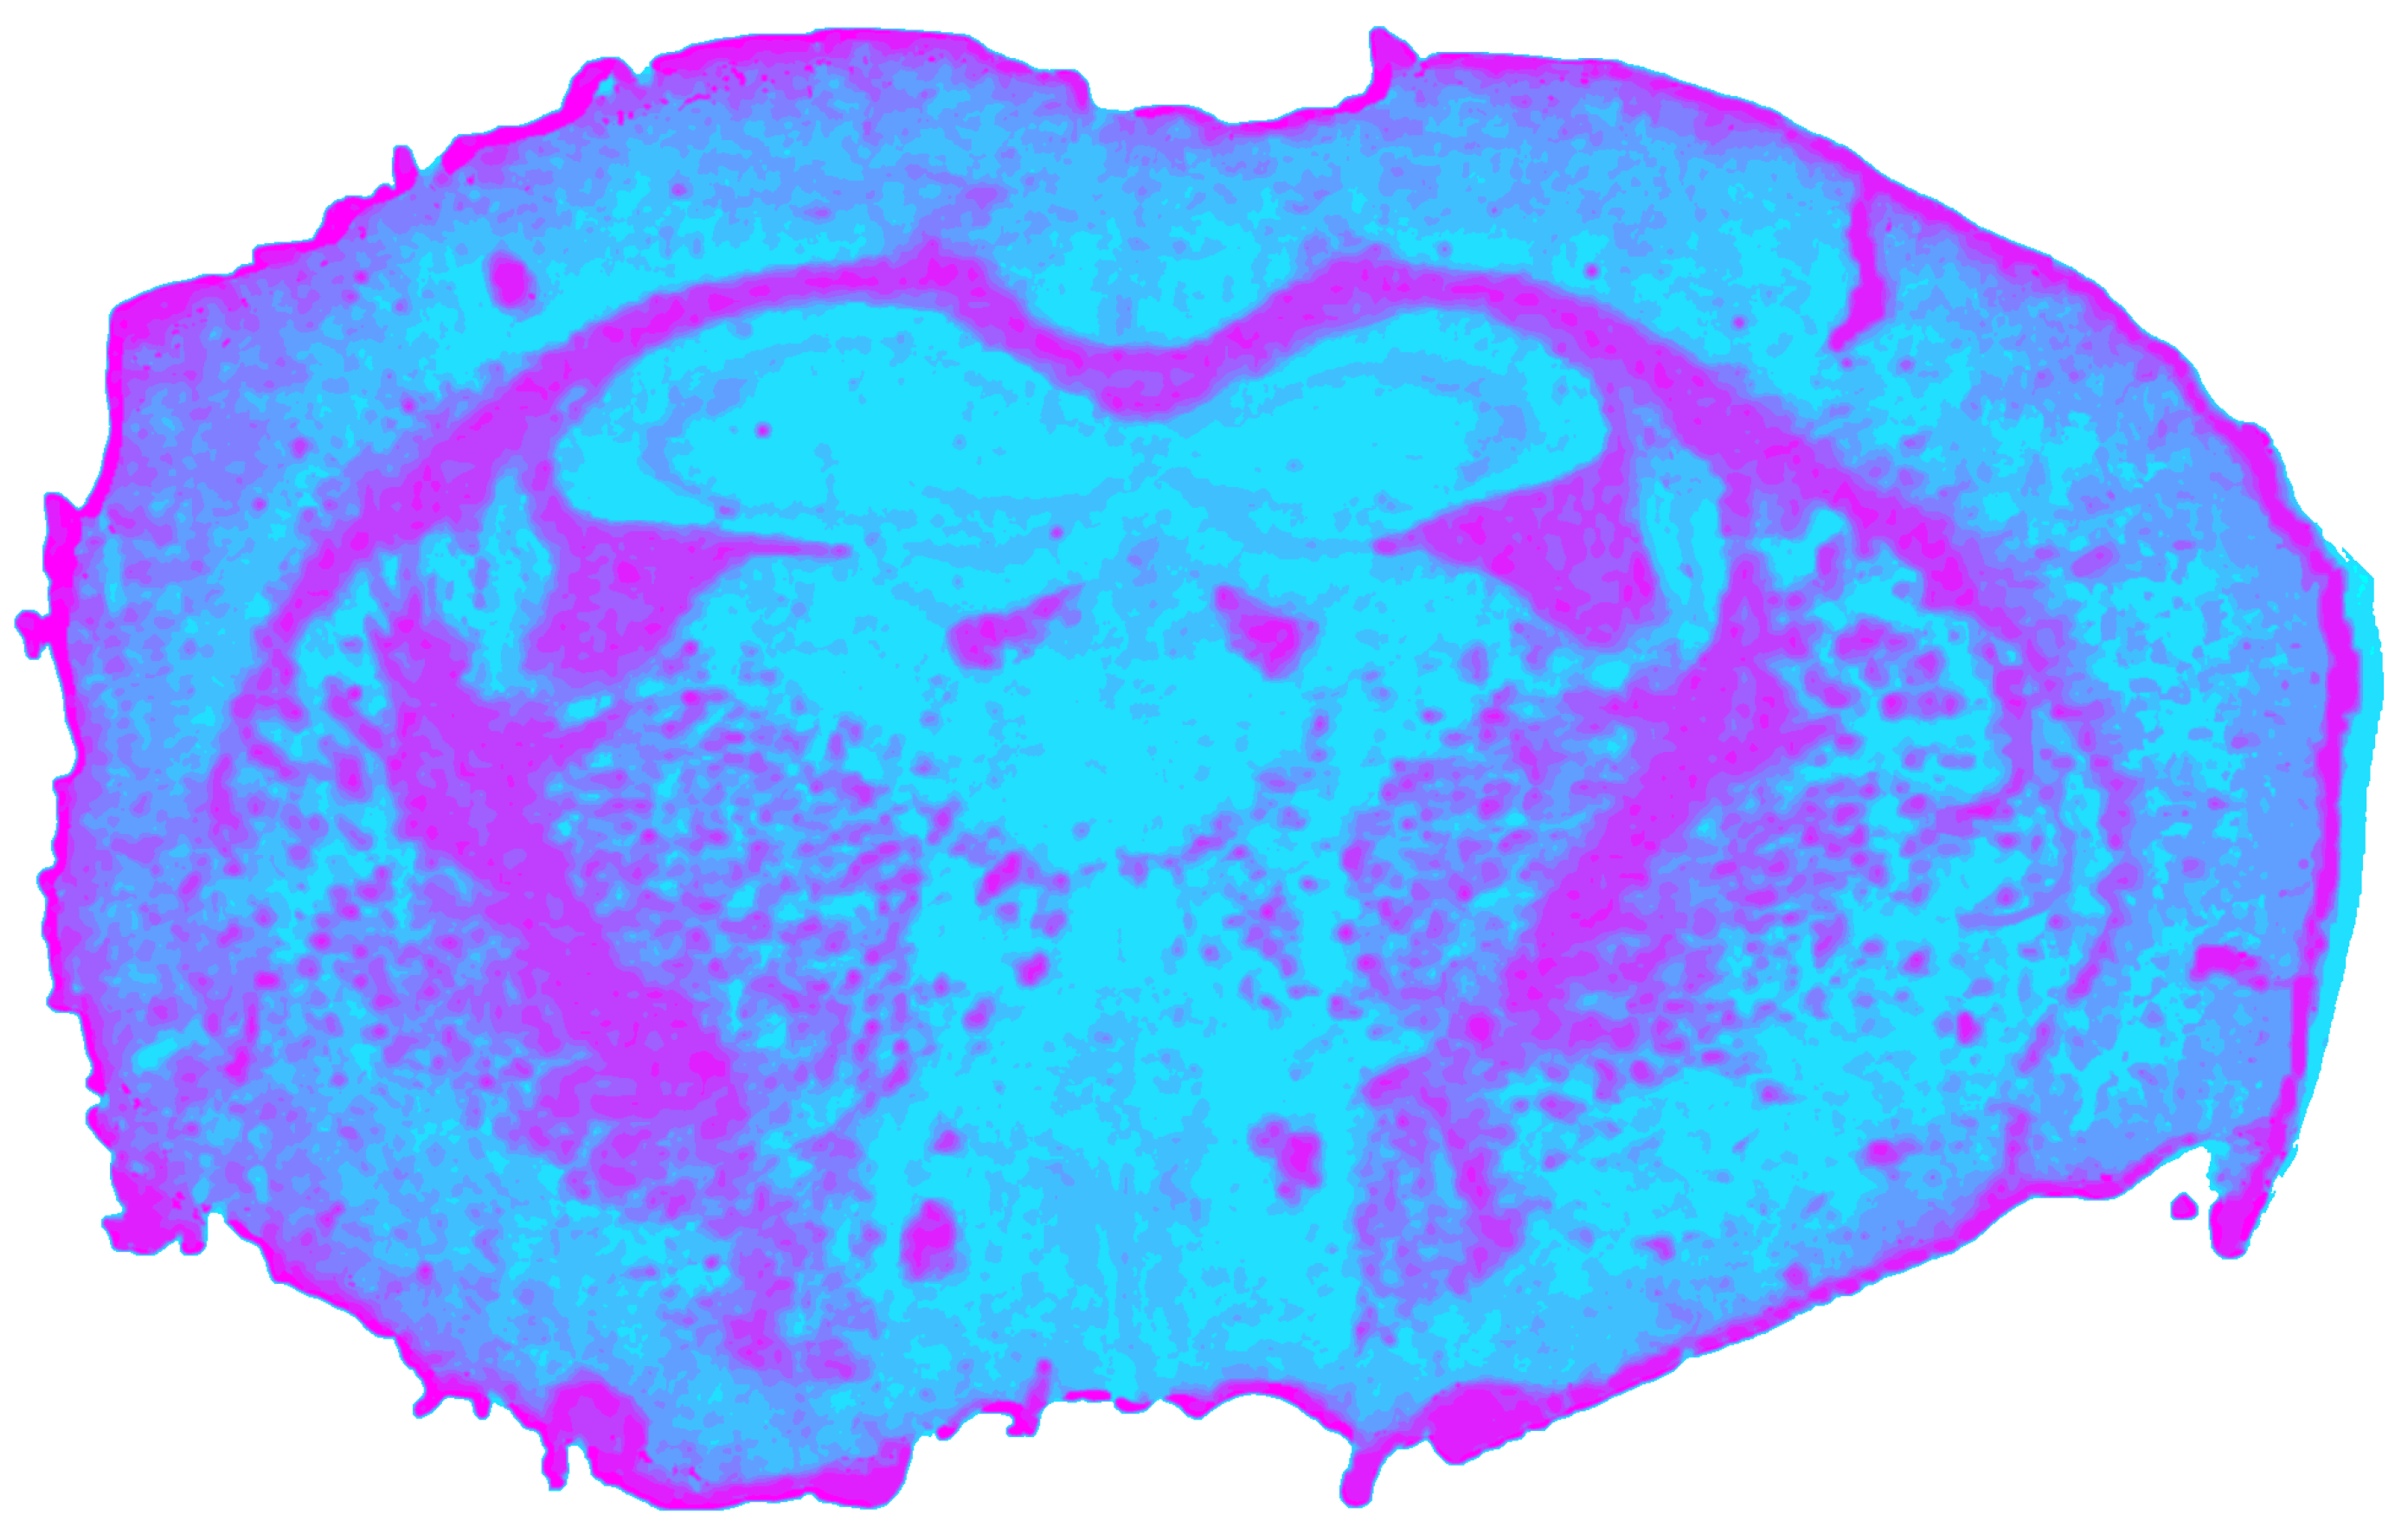

3.4. Fused-Data Processing Results

The fused dataset (Figure 8) was constructed by geometric registration of all modalities, concatenation of their spectral signatures, and global post-fusion normalization. The resulting high-dimensional datacube supported a joint clustering analysis yielding a silhouette value of sfused = 0.5420, which is slightly lower than those of the single modalities, reflecting increased internal cluster variability in the expanded feature space. Despite the reduced silhouette scores, fused segmentation enhanced anatomical completeness. Grey matter structures that were previously undetected or weakly visible, such as the hippocampus, thalamus, and hypothalamus, were consistently segmented in the fused cube. All major white-matter tracts were preserved. CSF structures appeared with mixed quality: the ventriculus tertius and hypothalamus were clearly delineated, whereas the ventriculus lateralis showed reduced contrast compared to MIR or RGB alone.

Fidelity of the fusion process was evaluated using the spectral correlation coefficient (SCC), which quantifies the correlation between original modality spectra and their corresponding spectra within the fused cube. SCC values were SCCNIR = 0.9999, SCCMIR = 0.9899, SCCRGB = 0.9999, indicating almost perfect preservation of modality-specific spectral characteristics after fusion. Mutual information (MI) between modalities further quantified cross-modal consistency. The fused dataset demonstrated markedly increased MI with all single modalities, most notably MI(NIR, Fused) = 1.5607, MI(MIR, Fused) = 1.0803, indicating that the fused cube captures complementary information unavailable to any single modality.

Figure 8. Spatial clustering map of the fused datacube obtained with Mini-Batch KMeans (k = 9), showing the unsupervised segmentation of the mouse brain section into spectral tissue classes. Colors are consistent across figures and represent categorical cluster labels.